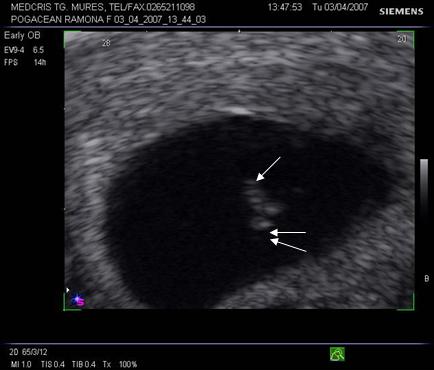

Fig nr. 69. Hematom

subchorial de dimensiune mare, langa orificiul cervical intern (cu sageata)

Fig nr. 70 Aceeasi sarcina ca in figura precedenta,la eco Doppler se observa lipsa fluxului sangvin in hematomul subchorial ( sageata)